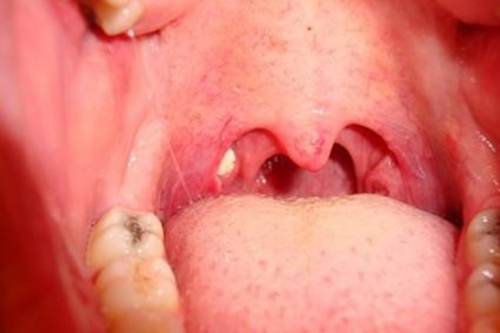

편도결석이란??

편도선에 자리한 작은 구멍인 편도에 세균이나 음식물찌꺼기가 뭉쳐서 돌처럼 굳어진 것을 말하며 이러한 편도결석은 냄새가 굉장히 역하고 한번 생기기 시작하면 반복되는 경향이 있습니다. 입냄새 뿐만 아니라 목의 통증이나 이물감을 유발하기도 합니다.

편도결석이 생기는 원인

원인은 다양한데 평소에 구강을 청결하지 않게 관리하여 구강내에 세균이 증식하는 경우도 있으며 편도선염, 비염, 축농증 등이 편도결석의 원인이 됩니다.